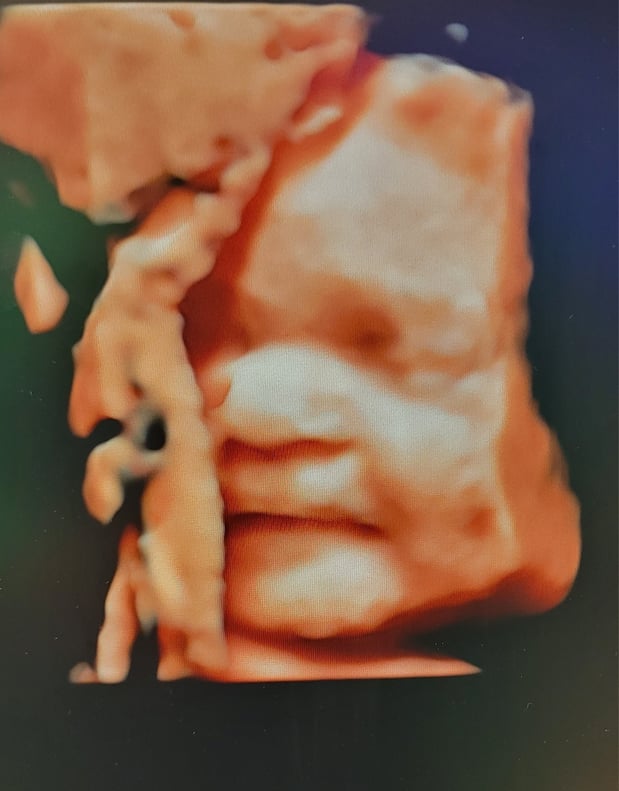

Tasha Crump, is registered by the American Registry of Diagnostic Medical Sonographers (ARDMS) and have over 18 years experience in medical diagnostic sonography specializing in Maternal Fetal Medicine. She is a highly proficient in the art of 3D 4D ultrasound. Tasha has practiced and trained in NYC's top ranked hospitals including Columbia Presbyterian. At Love at First Sight Imaging Studio you'll be in a very comfortable and calming atmosphere for you and your family to bond with your baby. We have state of the art equipment with HD Live to image unbelievably realistic views of your baby. You will fall in Love at First Sight.